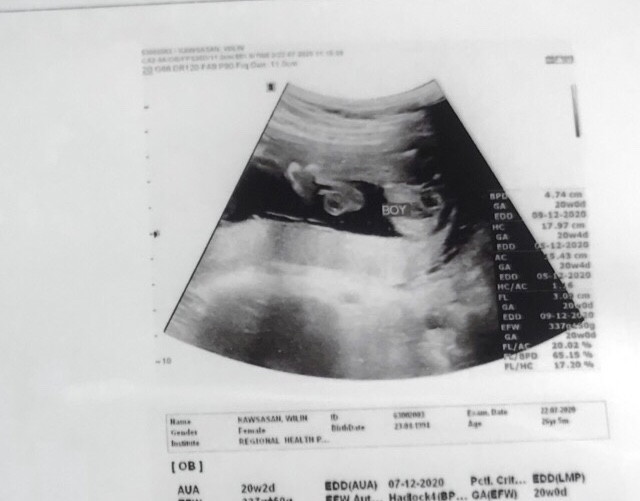

20 Week ได้ลูกชายค่ะ 🥰🥰

20w ลูกชายค่ะ👼